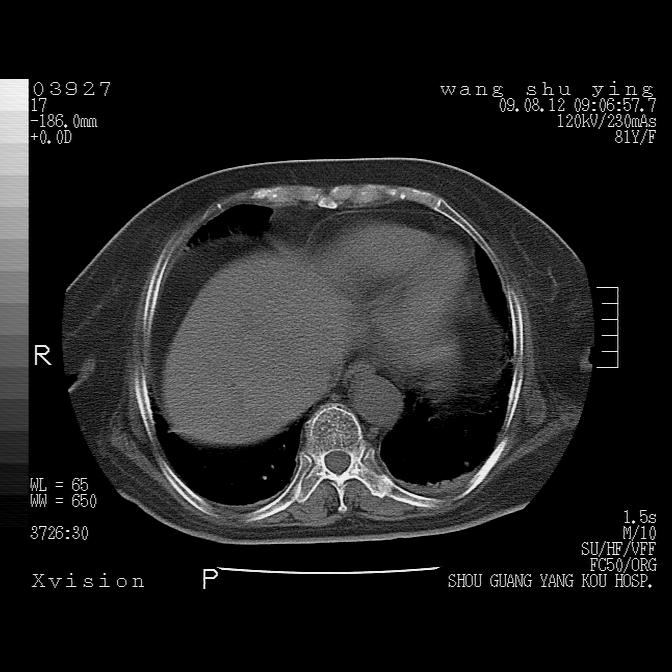

以下是引用帅河马在2009-8-12 12:59:00的发言:[br]两肺感染性病变伴双侧胸膜肥厚。[br]左侧甲状腺腺瘤不除外。[br]腹水+心包积液。[br][br][本贴已被 帅河马 于 2009-8-12 13:14:32 修改过]

以下是引用sdzyy在2009-8-12 18:17:00的发言:[br]两肺感染性病变伴双侧胸膜肥厚。[br]左侧甲状腺腺瘤不除外。[br]腹水+心包积液。[br]支持

以下是引用随光逐影在2009-8-12 19:42:00的发言:[br]1)两肺感染性病变伴双侧胸膜肥厚。2)不排除左侧甲状腺腺瘤。3)肝脏占位性病变;建议行进一步检查。